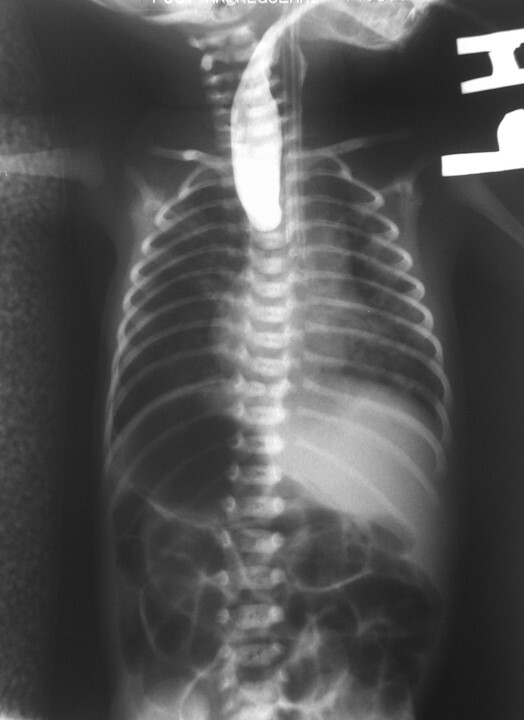

What pathology is shown here?

Esophageal Atresia